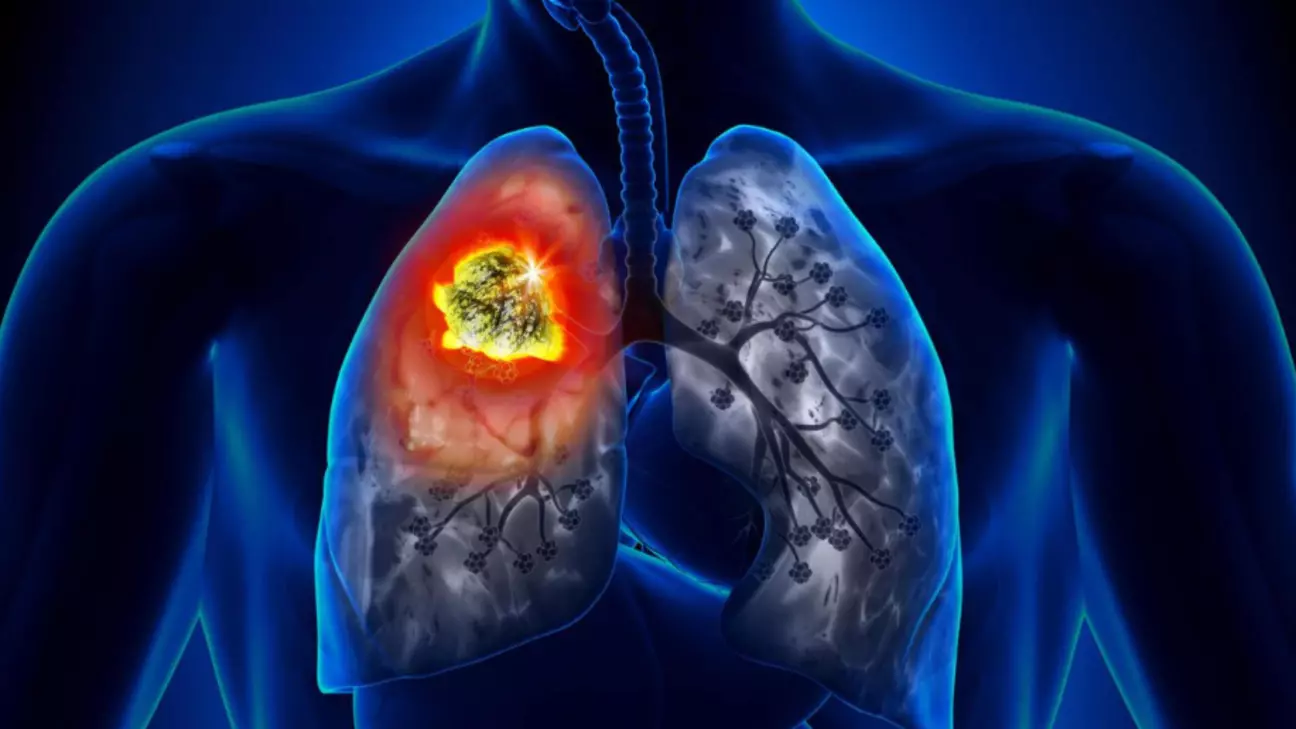

Рак легенів — це злоякісне утворення, яке починається з клітин легеневої тканини. Ця хвороба входить у трійку найпоширеніших онкологічних захворювань у світі.

Уявіть собі, що рак — це вогнище. На ранніх стадіях це маленьке займання, яке легко загасити. На пізніх — вже справжня пожежа, що охопила багато ділянок.